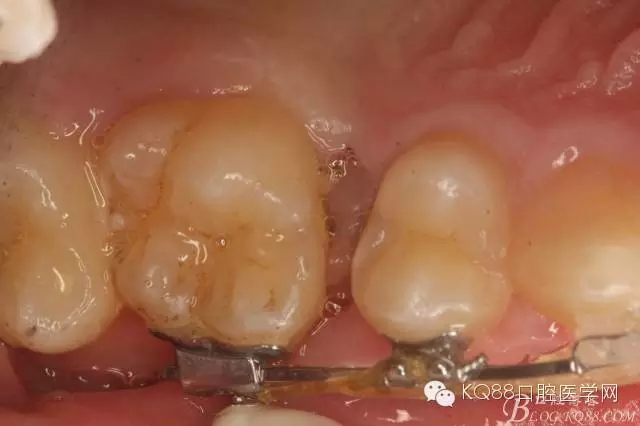

圖1.術(shù)前患者的口內(nèi)照片:16與14之間有約2mm間隙,矯治器已經(jīng)安裝到位。

圖2.從合面觀:16與14之間的牙間隙牙齦顏色異常,建議拍根尖片。